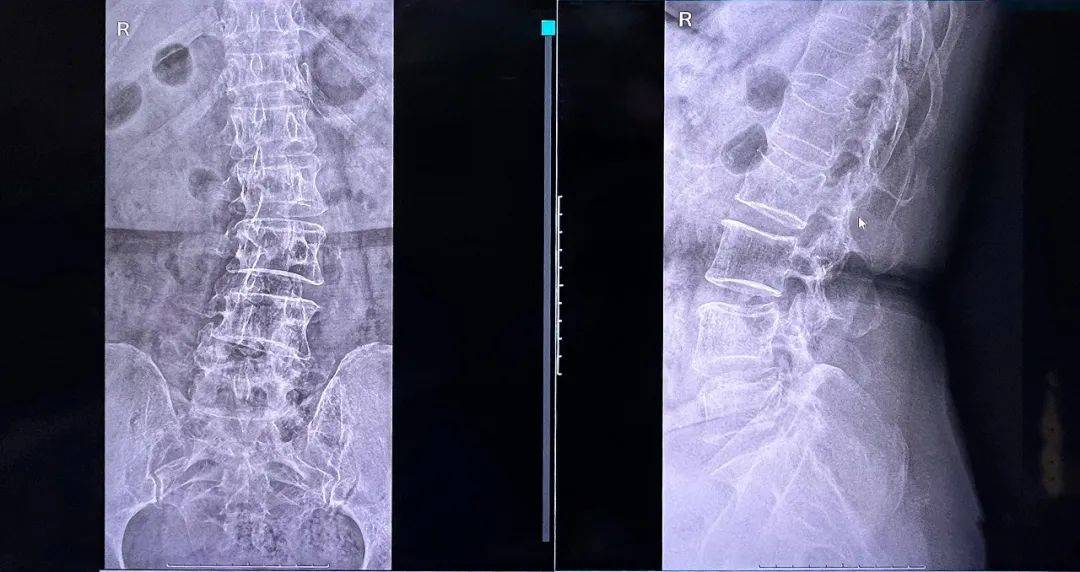

骨水泥在椎體內(nèi)的彌散效果良好,注入量充足、無(wú)滲漏。整體手術(shù)時(shí)間縮短,讓患者在本院獲得好的治療。